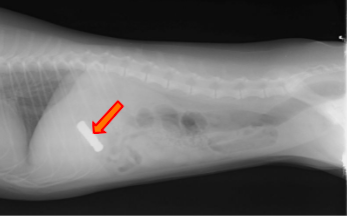

シェルティ(生後9か月、雌)

下痢を主訴に来院。この時に撮影したレントゲン画像が下の二枚です。

矢印で示したものは、金属類の異物だと思われます。

この異物が胃の中に留まっていました。